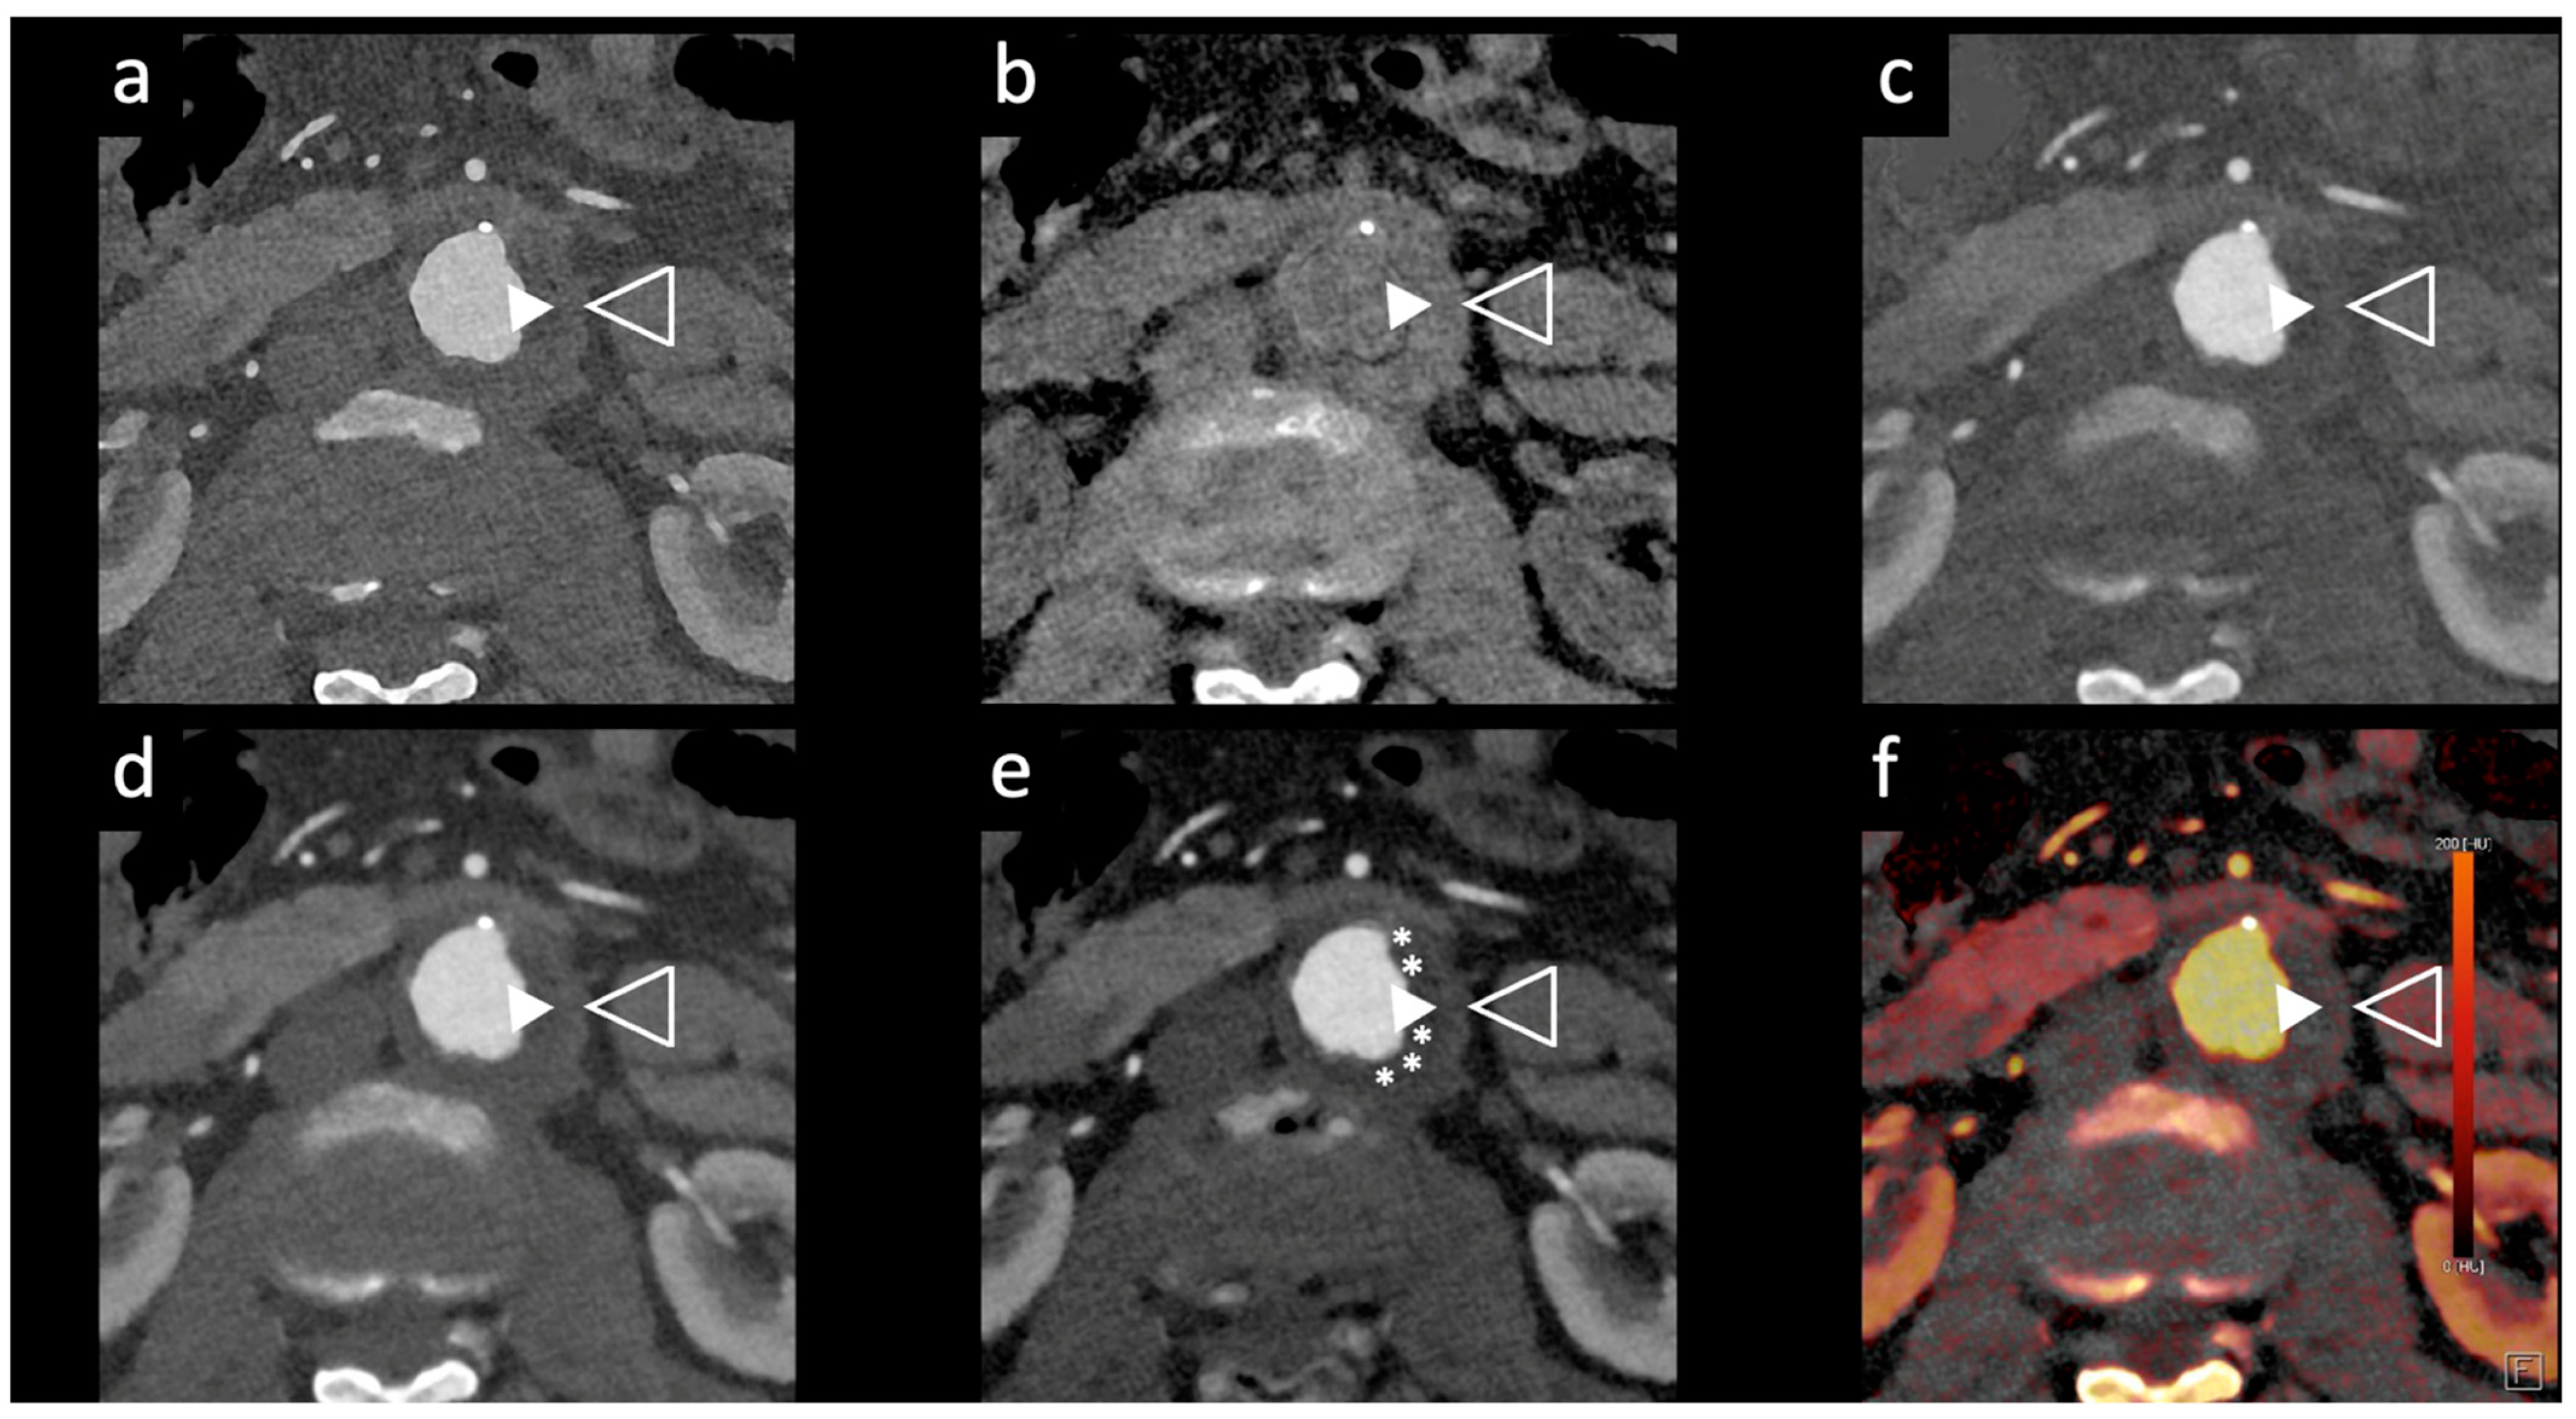

Figure 2. Comparison of image quality of an abdominal aortic aneurysm evaluated with photon-counting CT and standard contrast media (axial images). A thickened aortic wall related to aortitis (between solid and empty arrowhead) and intraluminal thrombotic stratification (* white asterisks) are visible at the level of the abdominal aortic aneurysm. High Resolution evaluation (Matrix 1024 × 1024) (a); Virtual Non-Contrast VCN (b); Iodine Map (c); 55 keV reconstruction (d); Pure Lumen reconstruction (e); Spectral Dual Energy Reconstruction (f). Department of Radiology, Fondazione Toscana Gabriele Monasterio, Pisa, Italy.

Dangelmaier et al. [11] explored the feasibility of PCCT with two contrast agents to detect endoleaks following EVAR. Using a specialized abdominal aortic aneurysm (AAA) phantom filled with a mixture of iodine, gadolinium, and calcium chloride, they were able to differentiate the distribution of these agents, enabling the reliable detection of endoleaks. Using an SPCCT prototype scanner with multi-energy bins, the results of this study showed that SPCCT has the potential to replace multiphase CT scans for endoleak detection without sacrificing diagnostic accuracy. It distinguishes endoleaks from calcifications in a single scan, thereby significantly reducing radiation exposure, which is vital in clinical settings (Figure 2 and Figure 3).

Rau et al. [14] presented a case study of an 81-year-old patient with incipient chronic renal failure who required contrast-enhanced aortoiliac CT angiography for follow-up imaging of an asymptomatic abdominal aortic aneurysm (AAA). They employed a first-generation PCCT scanner to reduce contrast agent use while maintaining diagnostic reliability. Utilizing a PCCT protocol with dual-source spectral image acquisition and dynamic monochromatic reconstruction near the K-edge of iodine, this study demonstrated a significantly reduced required contrast agent while preserving diagnostic confidence. This study shows promise for minimizing renal damage during imaging. However, further research is needed to refine these protocols and post-processing techniques. A similar case is shown in Figure 2 and Figure 5.